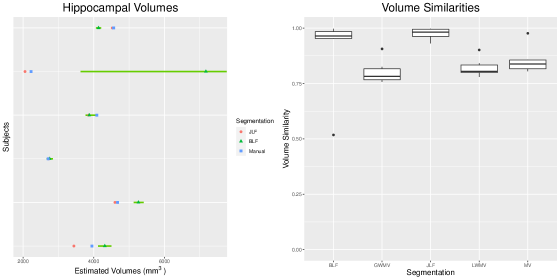

4.2 Aggregated Results

Here we present the results of using the control brain images as atlases for each of the six AD patients in our dataset. Figure 12 summarizes the volume estimates and volume similarities between the automatic and manual segmentations. In terms of volume similarity, our approach and JLF separate themselves from the three voting approaches. In addition to being competitive with the current state of the art, our approach is the only one that meaningfully produces measures of associated uncertainty, depicted in this case as 99% posterior credible intervals. This uncertainty is particularly evident in the second subject from the top depicted in the left panel of Figure 12. The point estimate (posterior mean) is quite far from the manually segmented volume relative to differences in the other brain images. However, the posterior distribution indicates a large amount of uncertainty about this particular estimate. Indeed, the MCMC trace plot of volume estimates for this subject (labeled 1263), displayed in Supplementary Figure 6, suggest that the marginal posterior distribution of volume is bi-modal. This is a feature of the posterior distribution that an optimization routine would likely miss. Lastly, we remark that even a trained expert will produce slightly different manual segmentations of the brain on two different occasions, so there is uncertainty associated with each manual segmentation itself. This is not quantified here. Thus it is impossible to assess any ‘significant’ difference between volume estimates from our proposed approach and a manually estimated volume.

These results demonstrate the feasibility of our approach on a full three-dimensional segmentation as well as additional useful information that would be unavailable otherwise. Posterior probability maps can be used to summarize where the hippocampus is likely to be. A simple thresholding rule yields image similarities that are competitive with the state-of-the-art when using healthy brains as atlases for diseased cases. However, thresholding is unnecessary when the goal is to estimate the volume of the hippocampus, as shown by the availability of a posterior volume distribution. Incorporating tissue class information into a generative Bayesian model for segmentation results in more faithful estimates of the hippocampal volume along with meaningful measures of uncertainty.